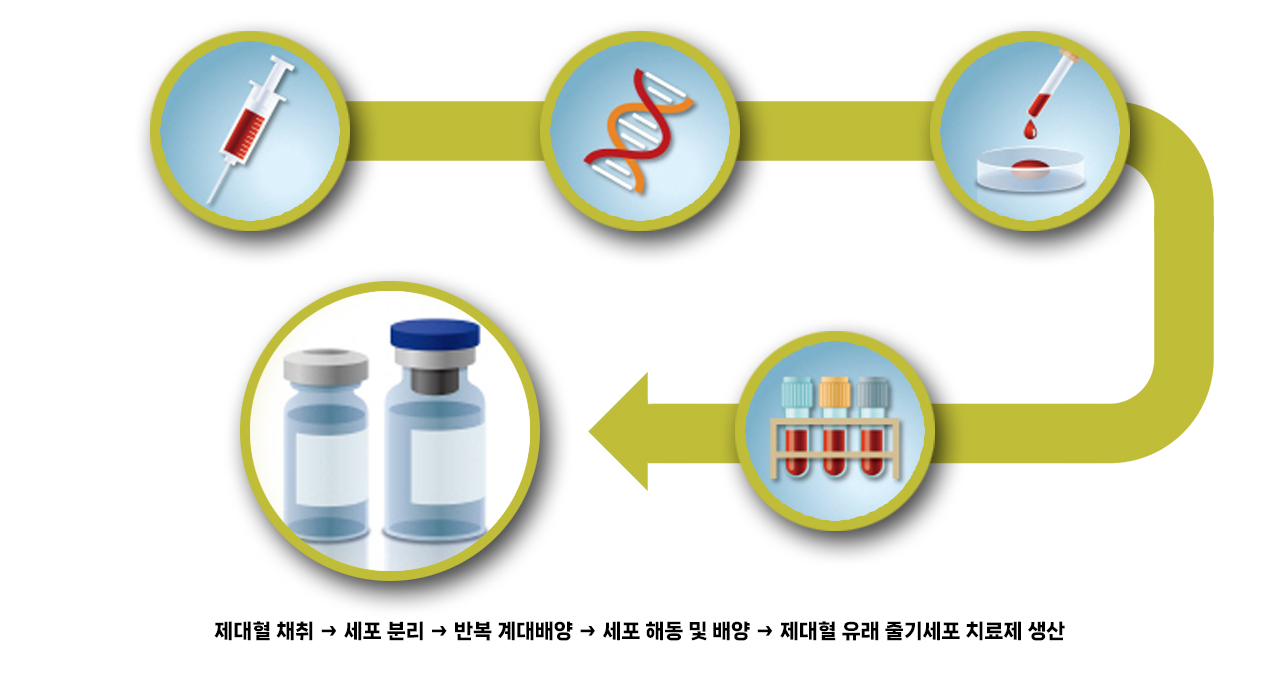

제대혈유래 줄기세포 치료제 생산과정

관절내시경이나 최소절개를 하여, 제대혈유래 줄기세포 치료제(카티스템)를 도포하여 치료